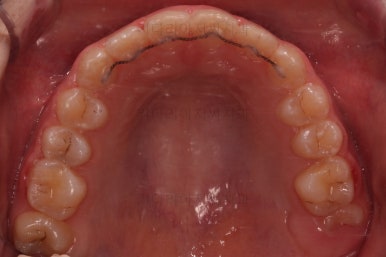

마무리를 해줍니다.

앞니 각도가 매우 좋아졌고요.(옥니 개선) 위 아래 앞니가 덮는 정도도 개선되었어요.(과개교합, 딥바이트)

엉성했던 어금니 맞물림도 매우 좋아졌어요.(앵글씨 2급 부정교합)

부산교정병원 전후사진을 비교해 볼게요.